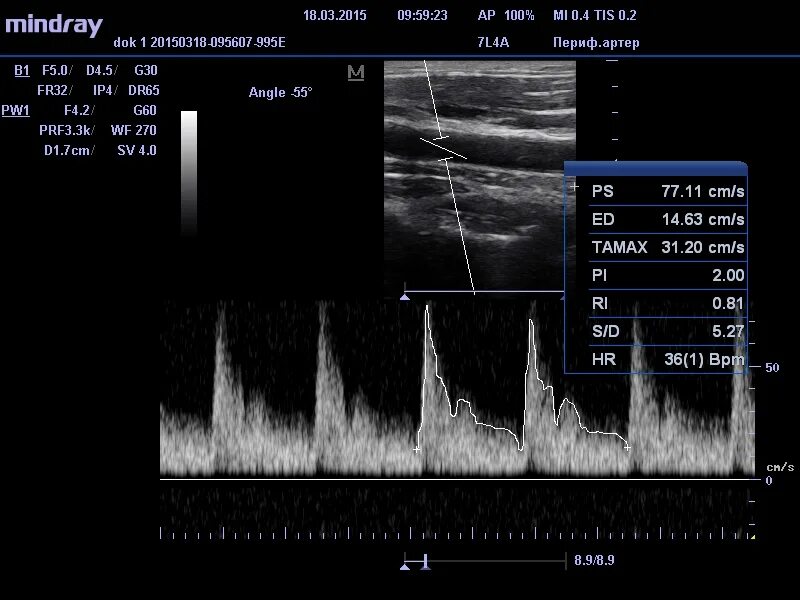

Ультразвуковая допплерография бца. Дуплексное ультразвуковое сканирование с допплерографией. Цдс бца. Вса на узи сосудов. Узи уздг брахиоцефальных сосудов.

Ультразвуковая допплерография сосудов (уздг). Цдс бца. Ультразвуковое триплексное сканирование. Цветное дуплексное сканирование (цдс). Цдс бца.

Дуплексное сканирование брахиоцефальных артерий бца ( уздг ). Узи уздг брахиоцефальных сосудов. Цдк триплексное сканирование сосудов брахиоцефального ствола. Уздг дуплексное и триплексное сканирование. Цдк триплексное сканирование сосудов брахиоцефального ствола.